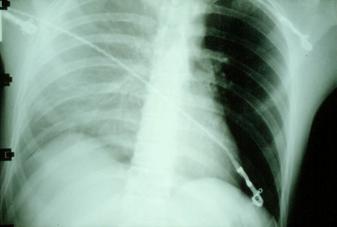

Pneumotorace sufocant bilateral Pneumotorace sufocant stang

Pneumotorace

sufocant stang Pneumotorace

sufocant drept Pneumotorace

sufocant drept